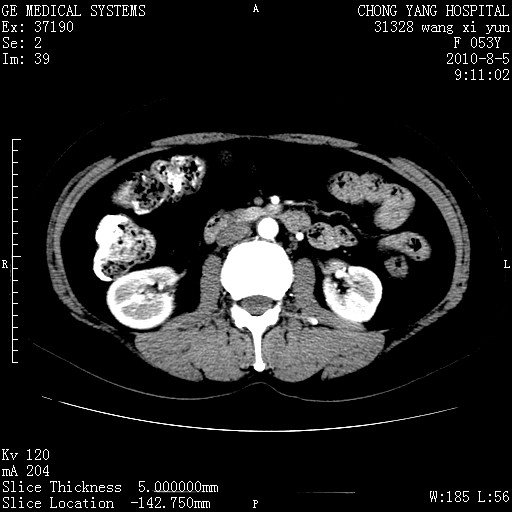

标题: CT28214:F41Y 血尿二十天,建议盆腔平扫加增强。

1)考虑肝左叶胆管细胞癌。2)脂肪肝。

支持胆管细胞ca。